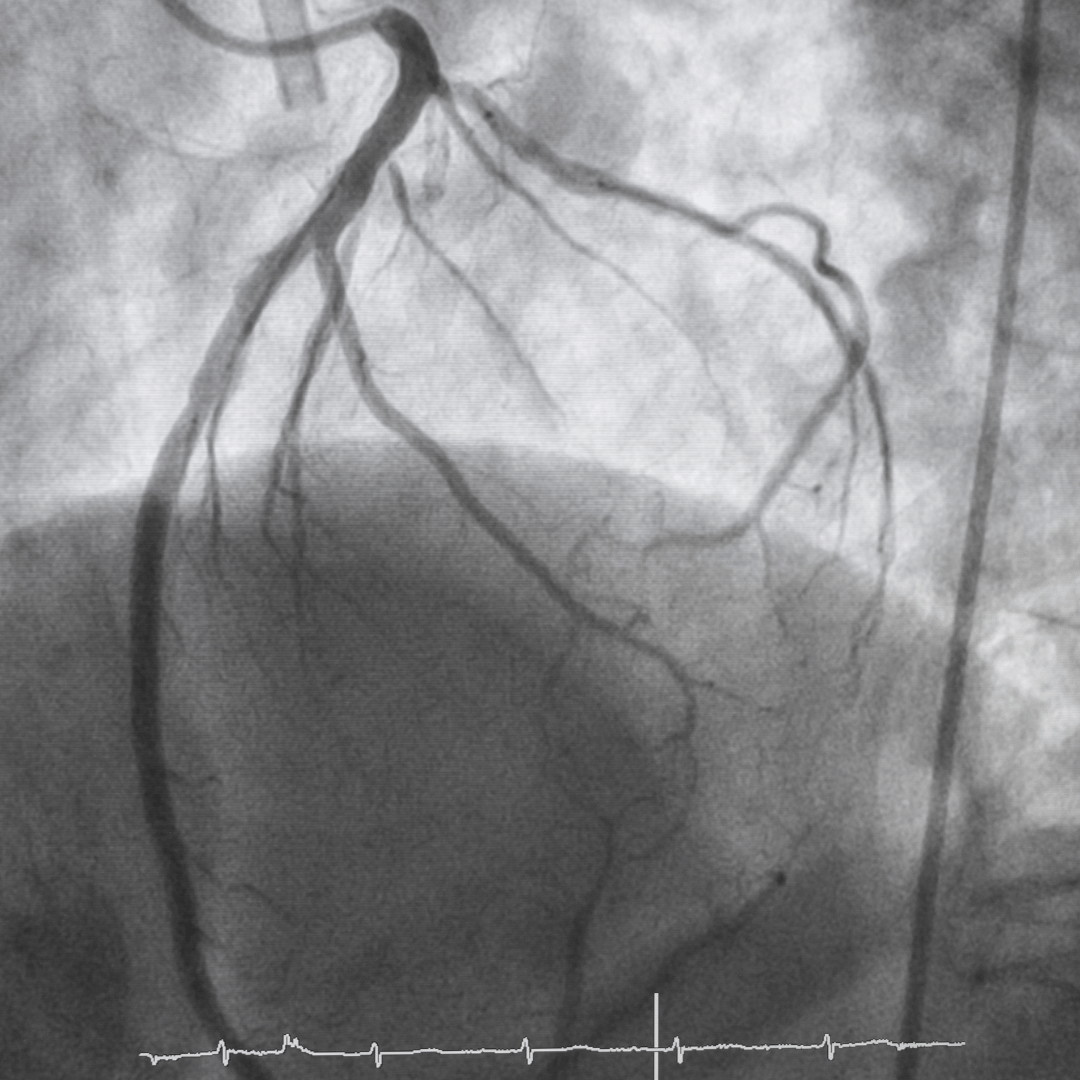

Coronary Angiography

Coronary angiography is the most accurate way of assessing the coronary arteries.

It is a minimally invasive procedure performed in a specialist cardiac catheter laboratory. A very fine tube (catheter) is inserted, most commonly through the wrist (radial artery), and guided to the heart under X-ray guidance.

Contrast dye is injected to allow us to see:

• Whether arteries are narrowed or blocked

• How severe the narrowing is

• Which part of the heart is affected

• Whether intervention would improve symptoms or prognosis